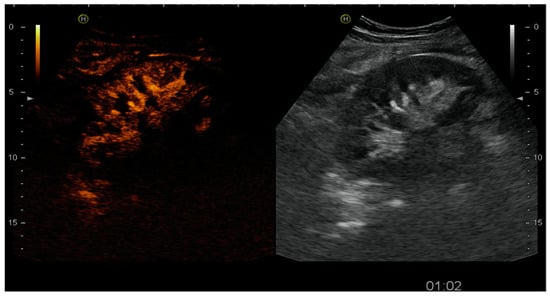

4.1.4. Infectious Complications